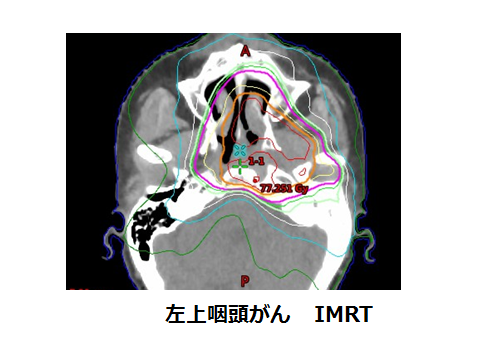

Https Www Jastro Or Jp Medicalpersonnel Guideline 2016 03cervicofacial Pdf

放射線治療 頭頸部がん 九州大学病院のがん診療 九州大学病院 がん

がん診療 放射線治療科 横浜市立大学附属 市民総合医療センター